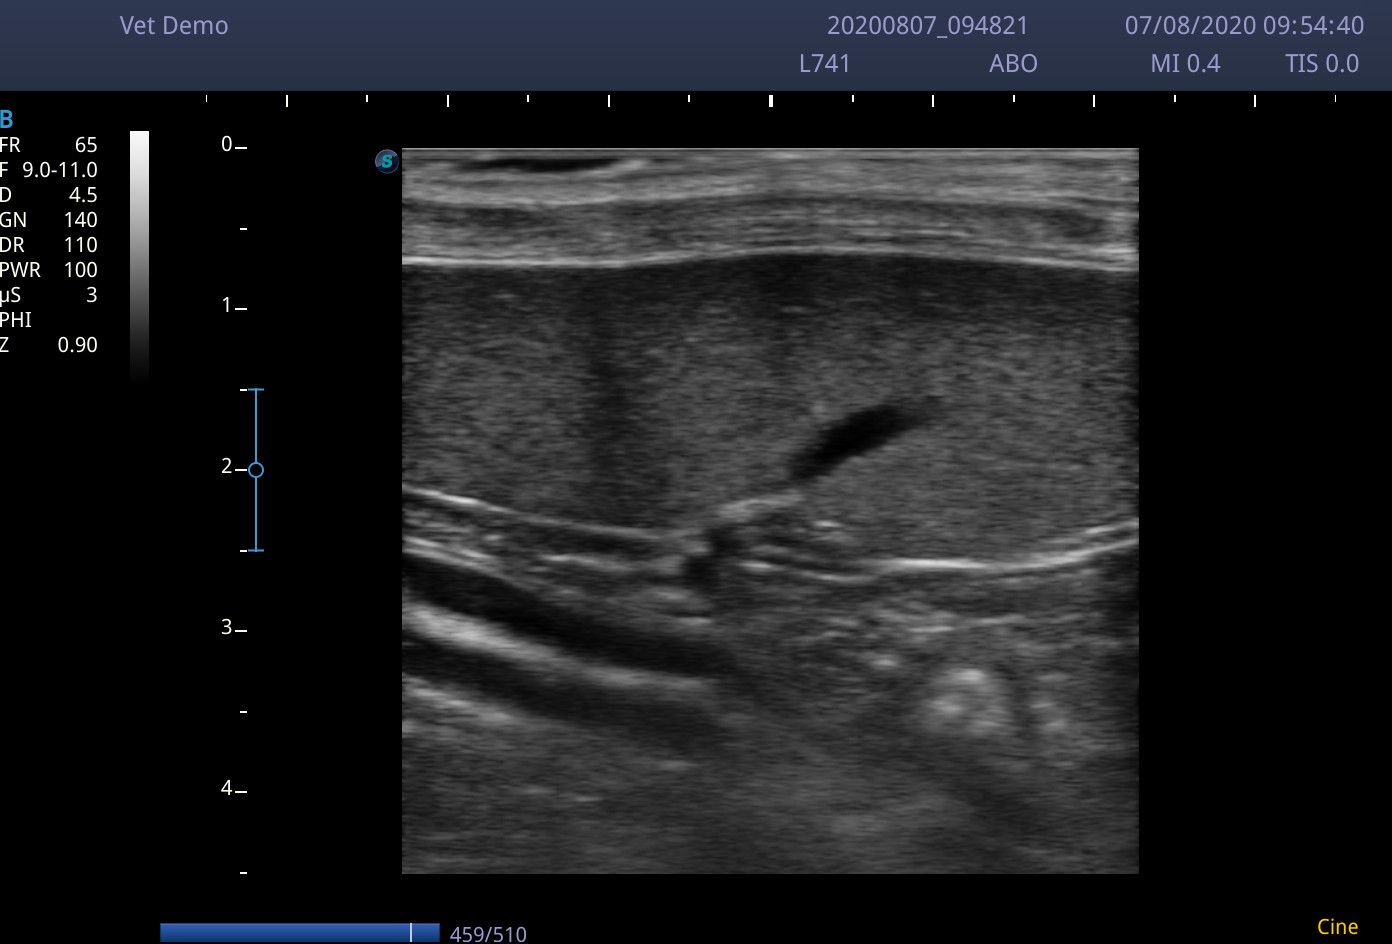

I scanned with the microconvex C613 probe (4-13MHz) and the linear L741 (4-16MHz). Although the linear probe gives great images, the 4.5cm footprint does make maneuverability around a small cat abdomen a little tricky. The microconvex probe was used in a few dogs up to 20Kg and managed to view the liver perfectly well.